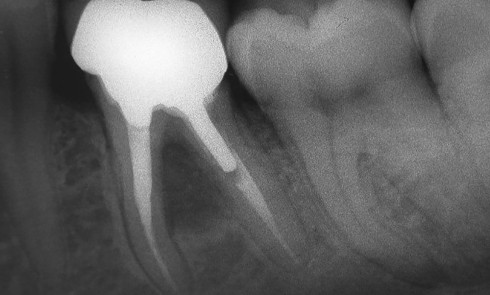

Article réservé à nos abonnés Conserver, extraire : quelles sont les limites ? Point de vue endodontique

Conserver ou extraire une dent est un dilemme quotidien du praticien qui doit pouvoir offrir une solution pérenne à son...